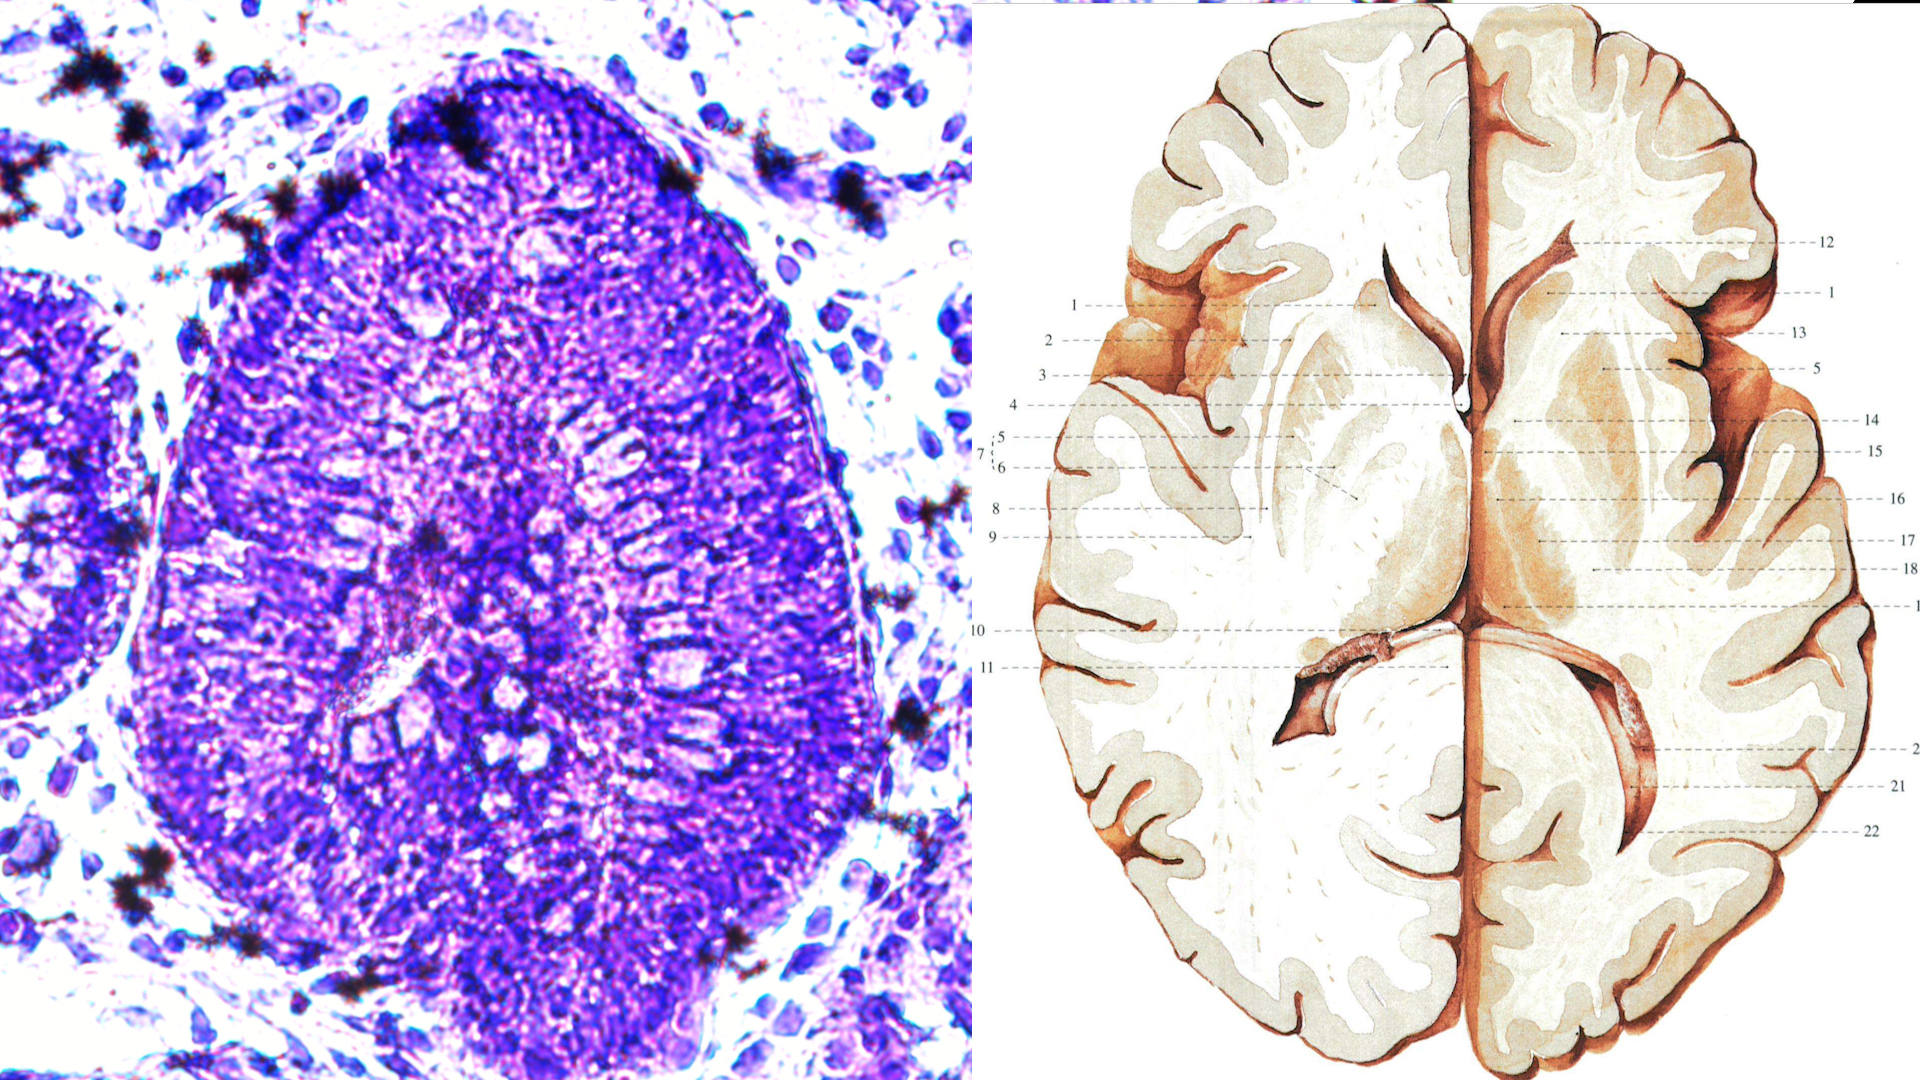

镁伽与赛拉达生物合作,已实现高通量标准化大规模类器官培养和测试,并与多家医院及药企开展合作研究,现已成功培养出具有2波段跳动和显著腔室结构的心脏类器官、具有脑室和清晰神经结构的脑类器官等数十种具有极高价值的类器官模型;此外,公司还将深度学习应用于类器官的电生理分析和实时检测,实现活细胞水平的定性定量分析和活细胞动态示踪等功能,可实时检测药物对多种类器官联用下的药效毒理影响,为药物研发和毒性测试等提供新的工具。

类脑的形成